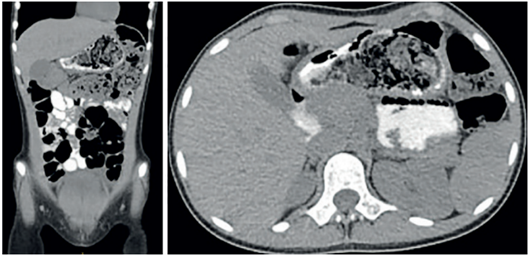

En las imágenes de la tomografía, se observó una lesión endoluminal gástrica de características heterogéneas, con diferencia de densidades (Figura 1), por lo que se realizó una endoscopia digestiva alta (EVDA) encontrando un cuerpo extraño, localizado en el cuerpo y antro gástrico (Figura 2), lo que confirmó el diagnóstico de tricobezoar.